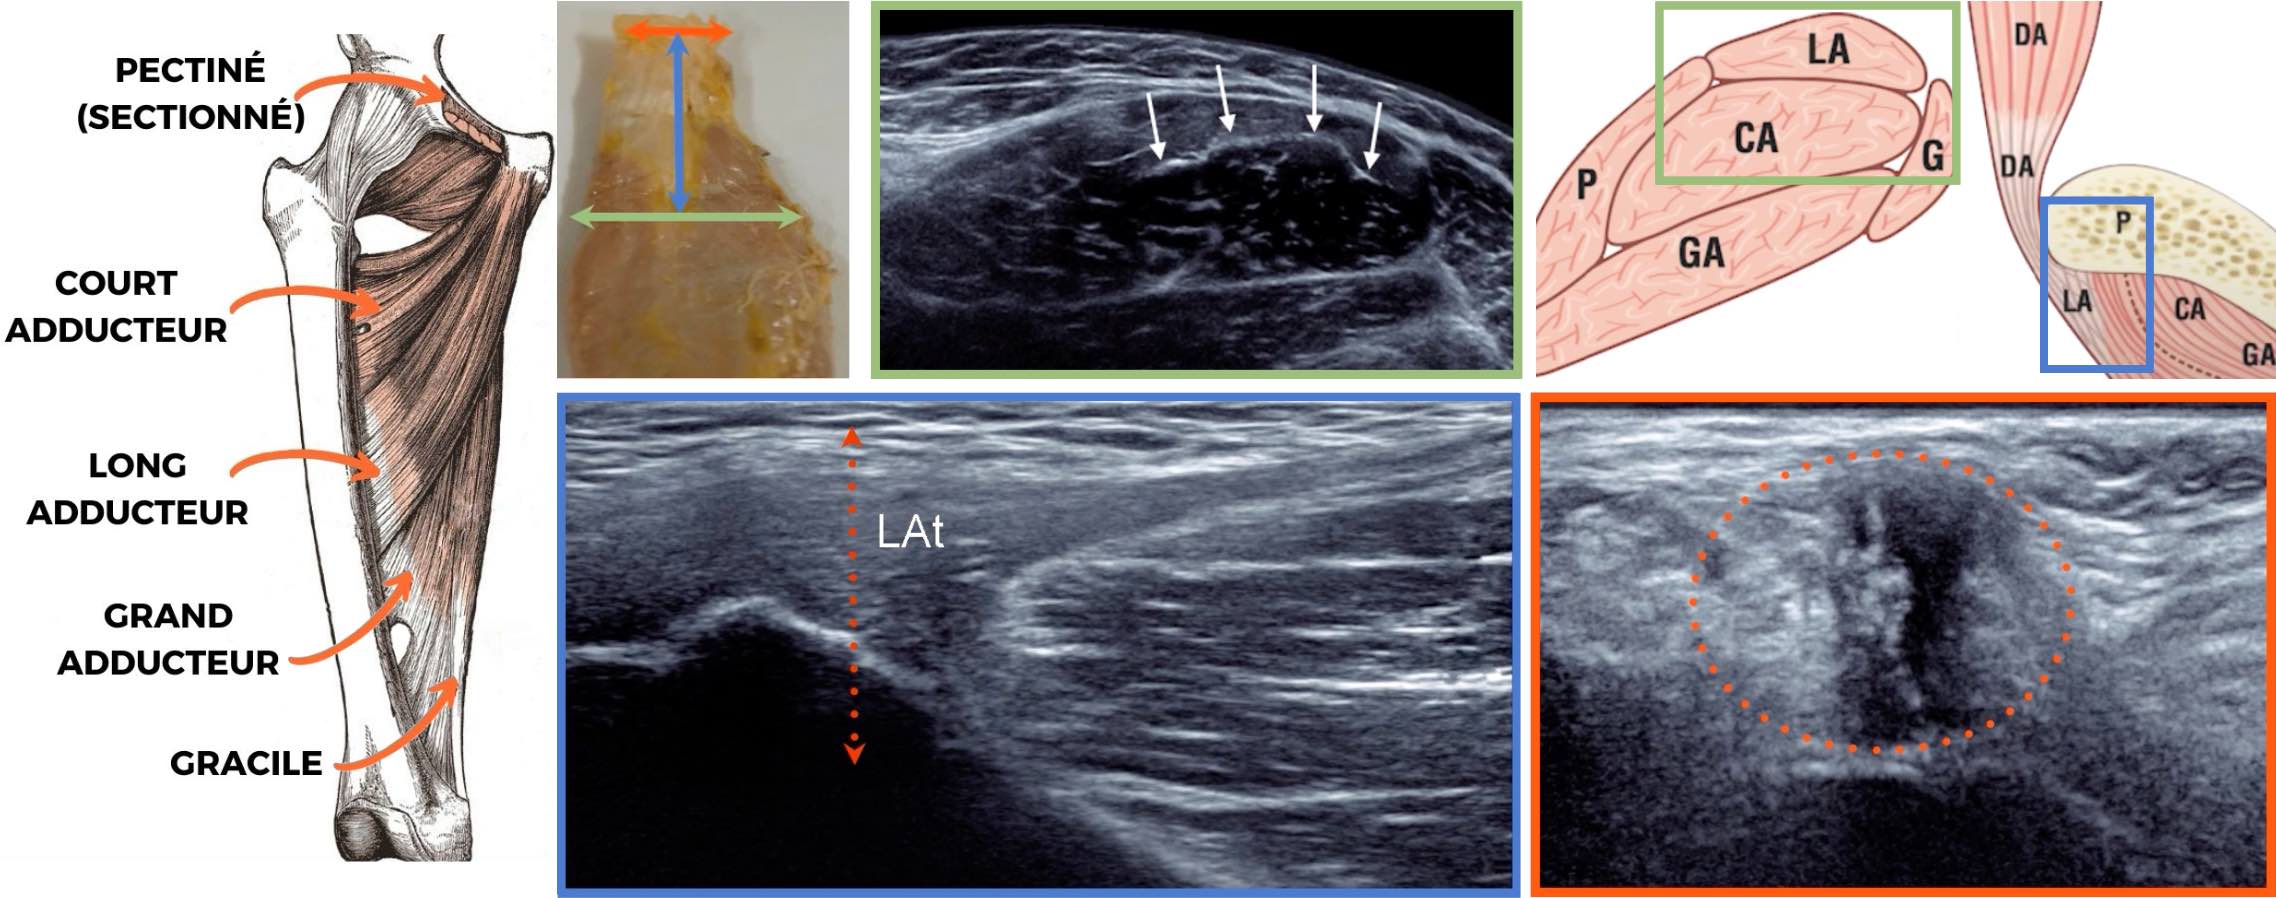

Pas d'épanchement articulaire coxo-fémoral.

Pas d'argument pour une fissure de l'enthèse du muscle long adducteur.

Pas de lésion traumatique de la jonction myotendineuse du muscle iliopsoas.

Intégrité du muscle droit fémoral et de ses insertions tendineuses.

Intégrité des tendons glutéaux et de l'insertion proximale des ischio-jambiers.

Pubalgie

Ebauches ostéophytiques péri-acétabulaires.

Pas d'épanchement coxo-fémoral abondant.

Pas de distension de la bourse ilio-pectinée.

Respect du tendon direct du muscle long fémoral.

Absence de hernie inguinale lors des manœuvres de Valsalva.

Pas d'anomalie de l'enthèse proximale des muscles adducteurs.